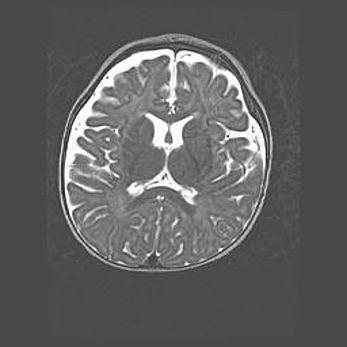

Лейкомаляция с кистозно-глиозной дегенерацией головного мозга.

Возраст: 2 месяца 25 дней

Вес: 6400 г

Окружность головы: 40 см

Срок гестации: 41 неделя

Лейкомаляцию относят к ишемически-гипоксическим повреждениям головного мозга, диагностируемым у новорожденных. При лейкомаляции в головном мозге обнаруживают очаги некроза, возникшие после тяжелой гипоксии и нарушения кровотока. В процессе морфогенеза очаги проходят три стадии: 1) развития некроза, 2) резорбции и 3) формирования глиозного рубца или кисты. Перивентрикулярная лейкомаляция (ПЛ) встречается примерно в 12% случаев среди новорожденных, обычно – у недоношенных детей, причем, частота ее зависит от массы, с которой младенец появился на свет. Наибольшее число малышей страдает лейкомаляцией, если масса при рождении 1500-2500 г.